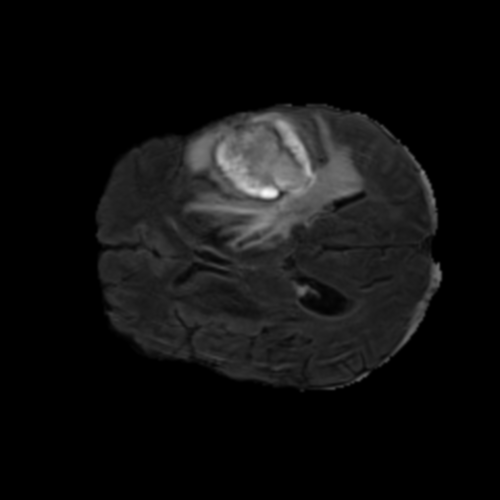

Ejemplos de Modalidades MRI

Visualización de las 4 modalidades de resonancia magnética y las segmentaciones de zonas tumorales utilizadas para entrenar el modelo

Glioma de Alto Grado (HGG)

FLAIR HGG

FLAIR

T1ce HGG

T1ce

T2 HGG

T2

T1 HGG

T1